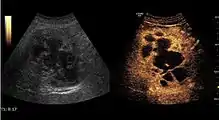

US examination is required to detect liver metastases in patients with oncologic history. In addition, the method can incidentally detect metastases in asymptomatic patients. Early identification (small sizes, small number) is important to establish an optimal course of treatment which can be complex (chemotherapy, radiofrequency ablation, surgical resection) but welcomed. In addition, discrimination of synchronous lesions that have a different nature is also important knowing that up to 25–50% of liver lesions less than 2 cm detected in cancer patients may be benign . US sensitivity for metastases detection varies depending on the examiner's experience and the equipment used and ranges between 40 and 80% . Sensitivity is conditioned by the size and acoustic impedance of the nodules. For a lesion diameter below 10 mm US accuracy is greatly reduced, reaching approx. 20%. Other elements contributing to lower US performance are: excessive obesity, fatty liver disease, hypomobility of the diaphragm, and certain patterns of hyperechoic or isoechoic metastases that can be overlooked or can mimic benign conditions. Conventional US appearance of metastases is uncharacteristic, consisting of circumscribed lesions, with clear, imprecise or "halo" delineation, with homogeneous or heterogeneous echo pattern. They can be single (often liver metastases from colonic neoplasm) or multiple. Echogenity is variable. When increased, they can compress the bile ducts (which may be dilated) and the liver vessels. Liver involvement can be segmental, lobar or generalized. In this situation a pronounced hepatomegaly occurs. Generally, metastases have non-characteristic Doppler vascular pattern, with few exceptions (carcinoid metastases). Cyst-adenocarcinoma metastases due to semifluid content may have a transonic appearance. When increasing, they can result in central necrosis. CEUS examination is a real breakthrough for detection and characterization of liver metastases.

Increased performance is based on identifying specific vascular patterns during the arterial phase and seeing metastases in contrast to normal liver parenchyma during the sinusoidal phase. CEUS increased accuracy is due to the different behavior of normal liver parenchyma (captures CA in Kuppfer cells) against tumor parenchyma (does not contain Kuppfer cells, therefore CEUS appearance is hypoechoic). To this adds the particularities of intratumoral circulation represented by a reduced arterial bed compared to that of the surrounding normal liver and the absence of the portal vessels . In terms of vascularity, metastases can be hypovascular (in gastric, colonic, pancreatic or ovarian adenocarcinomas) with hypoechoic pattern during arterial phase, and similar during portal venous and late phases, respectively hypervascular (neuroendocrine tumors, malignant melanoma, sarcomas, renal, breast or thyroid tumors) with hyperechoic appearance during arterial phase, with washout during the portal venous phase and hypoechoic pattern 30 seconds after injection.